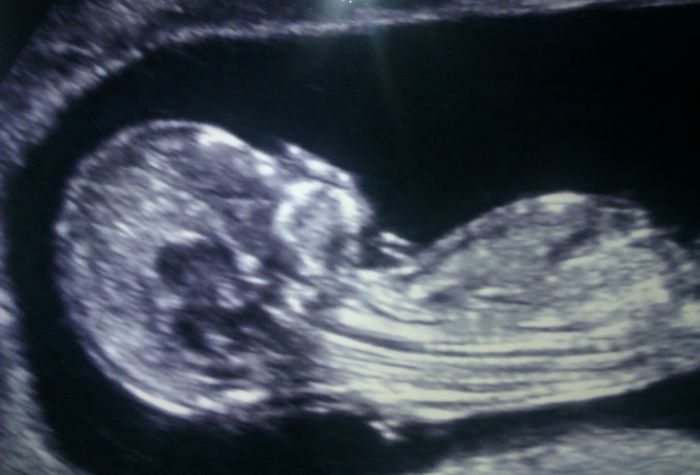

Já už jsem také pořád doufala, ale nedávala si tolik nadějí. Hlavně při tom IVF. nečekala jsem, že to vyjde. A je fakt, že to zklamání je aspoň menší a to překvapení o to větší :) Je tam už hezky vidět :) Víc vpravo má hlavičku :)

Ahojí...Kajdí neznameá když se vám to nepovedlo po tolika měsících že se to nepovede Smile Sestřenka měla od doktorů potvrzeno že je neplodná a nyní je v 16tt Wink špinění může mít víc důvodů Undecided takže nevím proč, sleduj to a uvidíš....hlavně to nevzdávejte Smile Chtěla si fotečku prcka tak ti jednu pošlu...to je fotka z pondělního screeningu.

Petule, to je neuveritelne, to je uplne hotovy clovicek, , vid? Clovek to samozřejme vsechno zna, ale kdyz to pak vidi, tak si uvedomi ten zazrak! Nadhera, moc gratuluju!! Ja jsem dnes, Anet, 20.dc a asi tyden po ovu. Dostat bych to mela pristi nedeli.